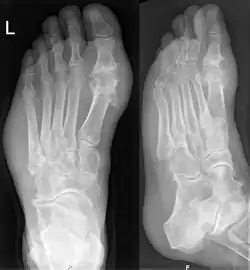

Gout may be diagnosed and treated without further investigations in someone with hyperuricemia and the classic acute arthritis of the base of the great toe (known as podagra). Synovial fluid analysis should be done if the diagnosis is in doubt.[17][50] Plain X-rays are usually normal and are not useful for confirming a diagnosis of early gout.[5] They may show signs of chronic gout, such as bone erosion.[46]

Gout on X-rays of a left foot in the metatarsal-phalangeal joint of the big toe. Note also the soft tissue swelling at the lateral border of the foot.